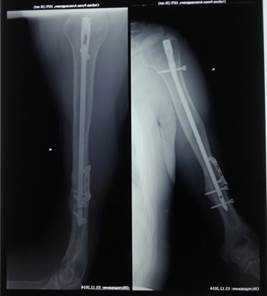

Больной С., 40 лет, госпитализирован в городскую больницу 24.12.2012 с сочетанной травмой после ДТП: закрытой черепно-мозговой травмой, сотрясением головного мозга, разрывом стенок толстой кишки, открытым переломом правой плечевой кости на границе ср/3 и н/3 со смещением отломков, травматической невропатией лучевого нерва. В экстренном порядке больному выполнены жизнеспасающие операции на органах брюшной полости. Первичный остеосинтез плечевой кости аппаратом внешней фиксации. Затем аппарат был демонтирован и выполнен окончательный реостеосинтез интрамедуллярным стержнем с блокированием. Послеоперационный период протекал без осложнений.

Через 4 мес. на контрольных рентгенограммах правой плечевой кости выявлен ложный сустав в зоне перелома. В неврологическом статусе - клиника полного нарушения проводимости правого лучевого нерва на уровне средней трети плеча. Активные разгибательные движения в правом лучезапястном суставе, пальцах правой кисти отсутствуют. По ЭНМГ выявлена грубая сенсомоторная дисфункция проведения по правому лучевому нерву.

Пациент госпитализирован в клиническую больницу № 122 им. Л.Г. Соколова, где 05.06.2013 г. выполнена операция - одновременная костная аутопластика ложного сустава правой плечевой кости и аутопластика большого дефекта лучевого нерва в средней трети плеча.

Под общим обезболиванием по старому послеоперационному рубцу, в средней трети, по наружной поверхности правого плеча, осуществлен доступ к плечевой кости, где обнаружен ложный сустав в месте перелома. Края кости обработаны, в них образован паз, куда был помещен отмоделированный фрагмент аутокости, предварительно взятый из гребня правой подвздошной кости. Костный аутотрансплантат фиксирован пластиной и 4 винтами.

С техническими трудностями в зоне перелома плечевой кости выделен центральный и периферический концы лучевого нерва. Центральный конец заканчивался невромой. После обработки концов нерва до отчетливых пучков, диастаз между ними составил 6 см. Выполнение состоятельного шва нерва с таким диастазом - не представлялось возможным. Для восполнения дефекта лучевого нерва решено произвести аутопластику. Для этого с правой голени из разреза длинной 2 см в области наружной лодыжки специальным инструментом взят икроножный нерв с образующими его ветвями. Между концами лучевого нерва, с использованием микрохирургической техники, вшито 4 аутотрансплантата из икроножного нерва, длинной по 7 см. Периферический конец лучевого нерва перекрыт полностью, а центральный на 3/4. Причем трансплантаты пришлось укладывать на металлическую пластину (рис. 1) и закрывать мягкими тканями.

На контрольных рентгенограммах правой плечевой кости - сросшийся перелом плечевой кости (рис. 3).

Рис. 3. На рентгенограмме больного С. сросшийся перелом плечевой кости